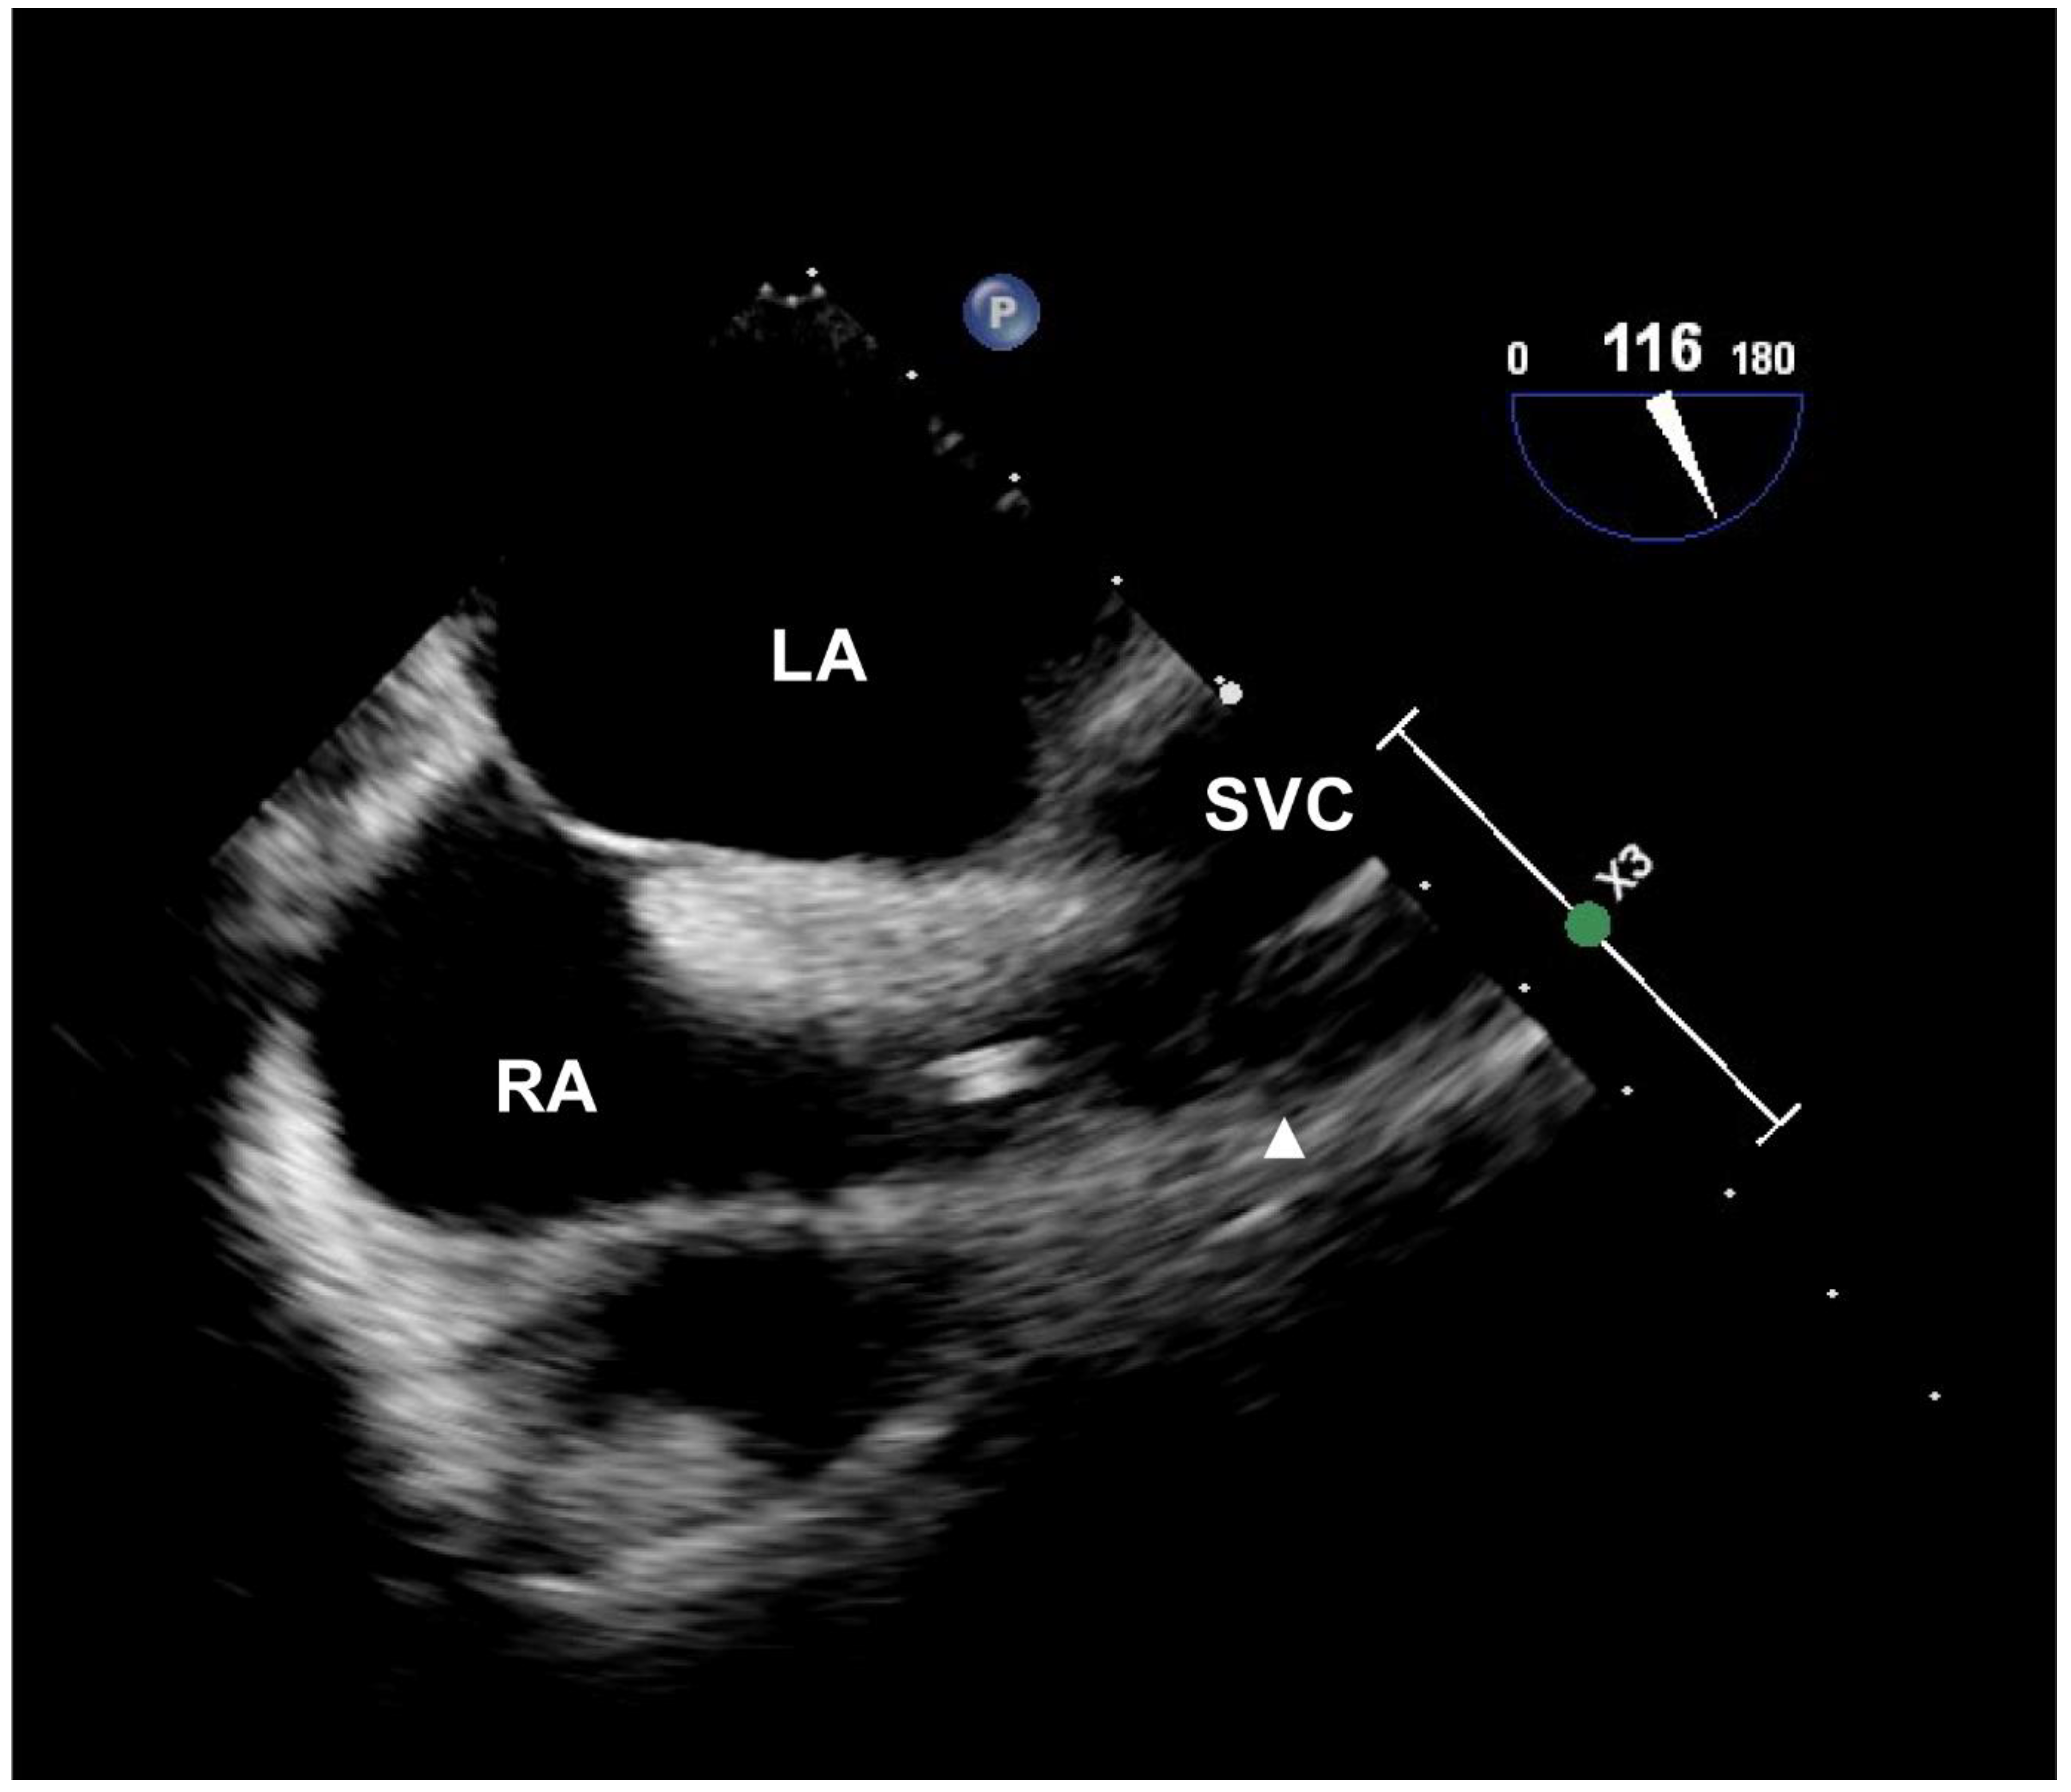

2.3. Procedure and Data Collection